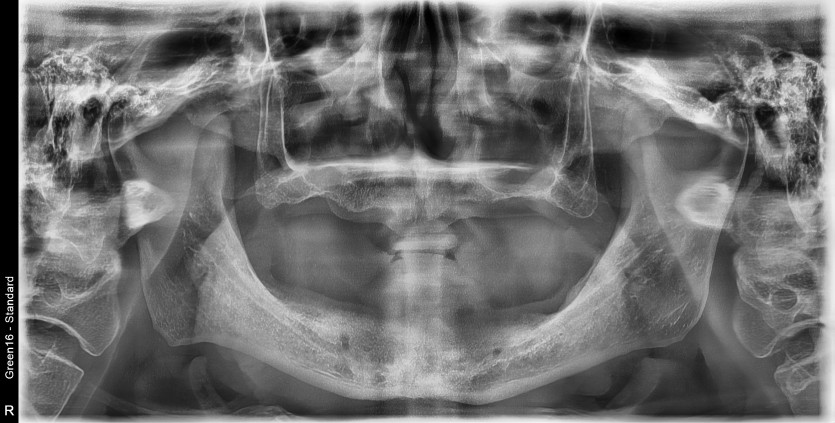

만 61세 전체 임플란트 증례(하악 풀아치)

전체 임플란트 증례입니다.

14개의 임플란트로 완성하였습니다.(하악 풀아치 진행)